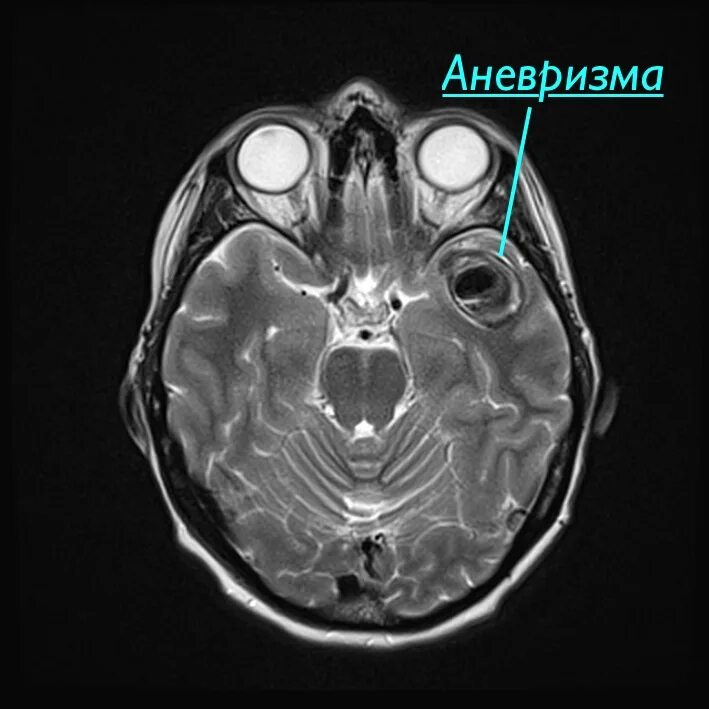

Аневризма головного мозга на кт